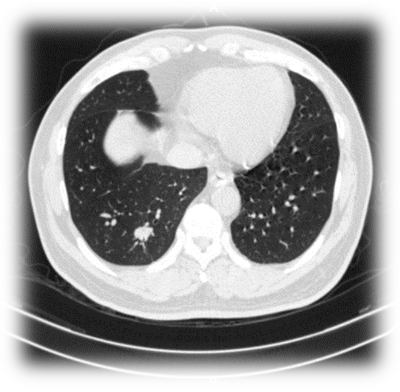

目前,肺癌是世界发病率第二、中国男性发病率第一的癌症,死亡率高居世界及我国首位。近年来,随着低剂量螺旋计算机断层扫描(low-dose computed tomography, LDCT)的广泛应用,越来越多的多发肺部结节被发现(我国检出率高达20%-80%)。由于许多高危肺部结节是癌前病变或早期肺癌征象,谈“结”色变成为了许多肺部结节患者挥之不去的心理阴影。

对于肺部结节的治疗,传统方法是以手术切除为主,但手术切除存在创伤大、难以重复、患者肺功能显著受损等不足,严重时易导致因过度手术治疗而直接影响患者生活质量。因此,如何以最优化的诊疗方式治疗肺部结节,尤其是多发肺部结节,是目前外科治疗领域遇到的瓶颈问题。

微波消融因其具备创伤小、恢复快、可重复治疗多个肺结节、能最大限度保护肺功能等优点,是解决以上外科治疗瓶颈问题的有效手段。

在CT引导下,医生将牙签粗细的微波消融天线经皮肤穿刺到肺部病灶部位,组织内极性分子在微波场的作用下高速运动,互相摩擦产生热量,在病变组织内迅速升温,肺结节病灶发生凝固性坏死, 2-3个月后这一坏死组织逐渐纤维化,最终被人体吸收,病灶消失。